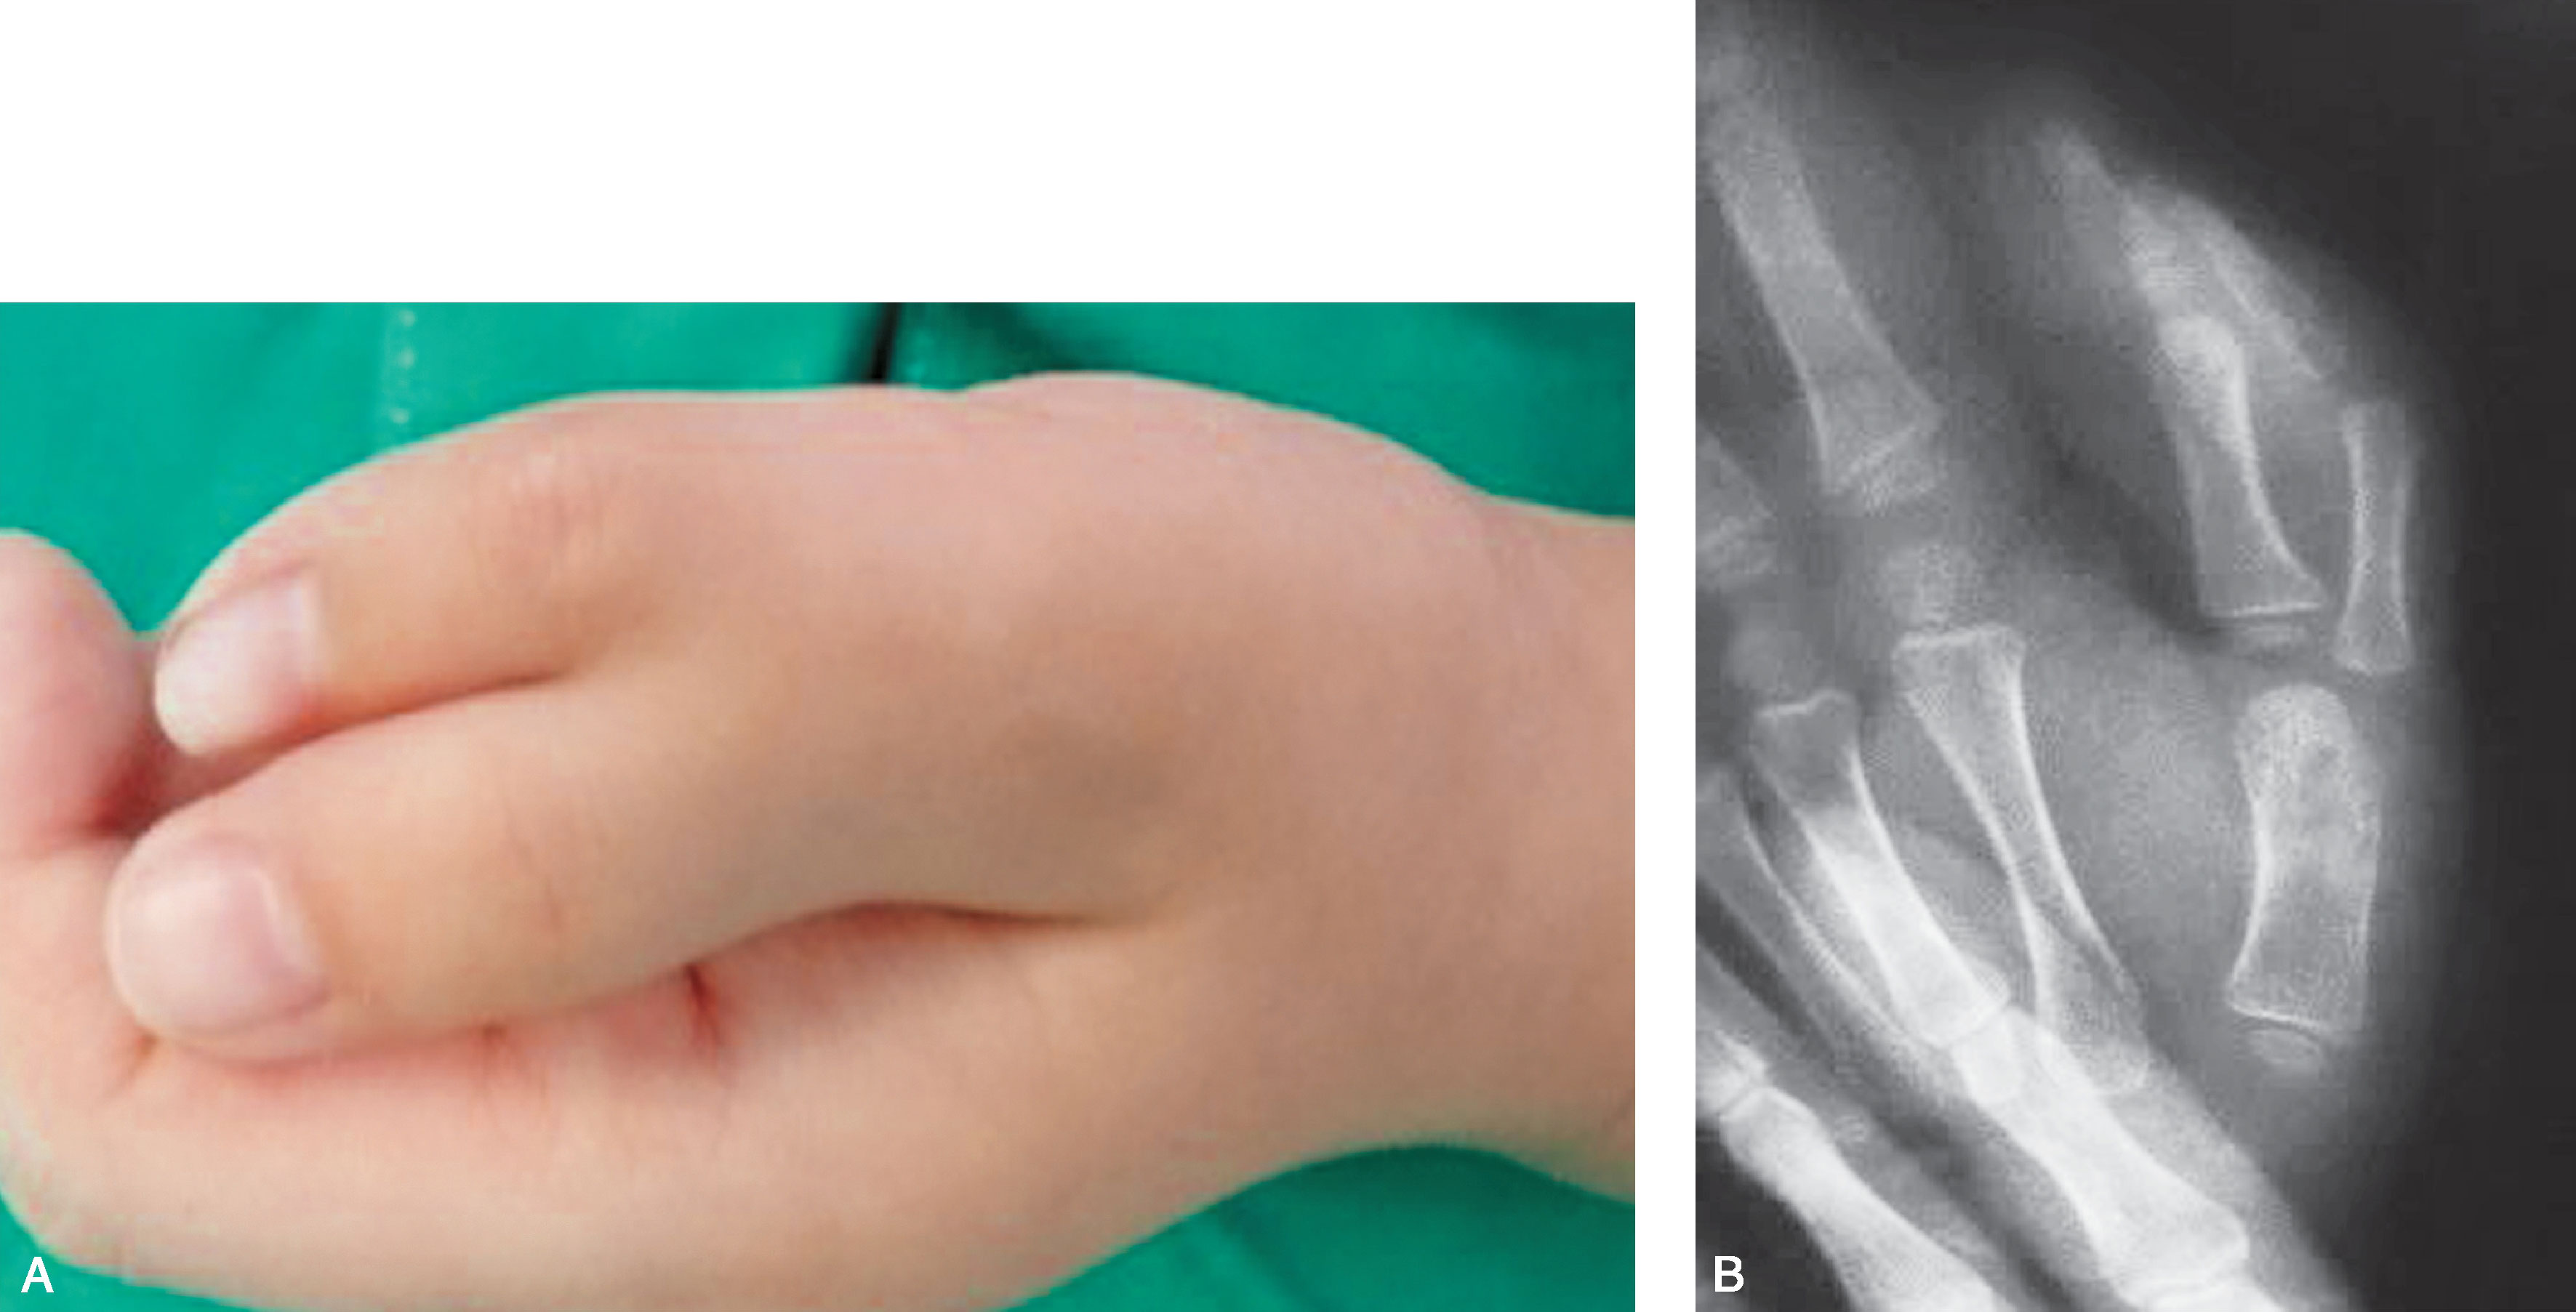

2.Ⅱ型 远节指骨完全分开,两个骨骺,近节指骨增宽,远端有两个关节面与近节指骨形成两个关节(图2-1-5~图2-1-11)。

图2-1-20 Ⅳ型病例1

A.左手多拇指,主、次拇指外形及大小相差较大;B.X 线片显示桡侧拇指骨关节结构明显发育不良,应切除桡侧拇指,术中重建保留的尺侧拇指的拇短展肌止点并紧缩掌指关节桡侧关节囊和侧副韧带